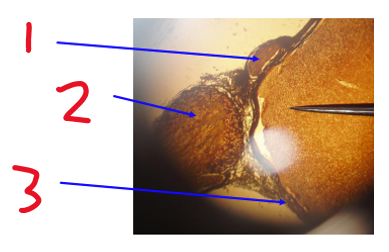

Name structure 1

Dorsal root ganglion

Name structure 2

Dorsal root

Name structure 3

Name structure 4

Name structure 5

Spinal nerve

Name structure 6

Ventral root

Name structure 7

Name structure 8